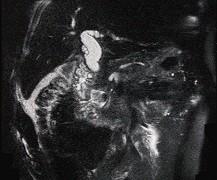

问题 男,78岁,阵发性上腹部疼痛10年伴呕吐,加重1年,影像检查如下图,应诊断为 ( )

选项 A.十二指肠癌 B.十二指肠憩室 C.十二指肠淋巴瘤 D.十二指肠结核 E.肠系膜上动脉压迫综合征

答案 B